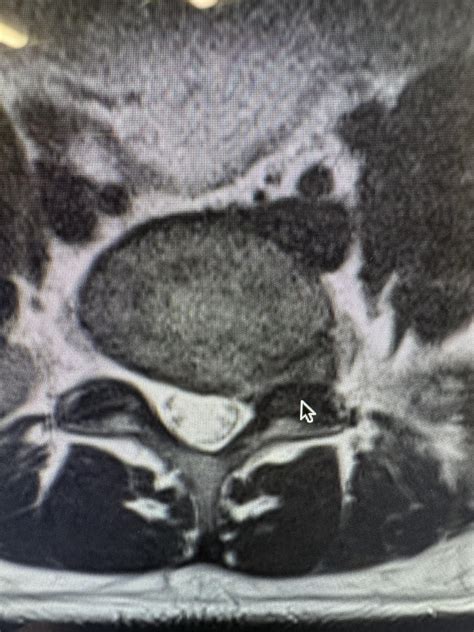

The human spine is composed of vertebrae cushioned by intervertebral discs. These discs act as shock absorbers, consisting of a tough outer layer called the annulus fibrosus and a jelly-like center known as the nucleus pulposus. In a healthy state, these discs are filled with water, which allows them to remain supple and resilient. Multilevel disc desiccation occurs when these discs lose their water content, leading to a loss of disc height and structural integrity across several segments of the spine.

When multiple discs are involved, the process is classified as "multilevel." This is distinct from a single-level issue because it implies a broader wear-and-tear process, often associated with degenerative disc disease. As the discs dehydrate, they become less effective at absorbing impact, which places increased mechanical stress on the surrounding ligaments, facet joints, and nerve structures.